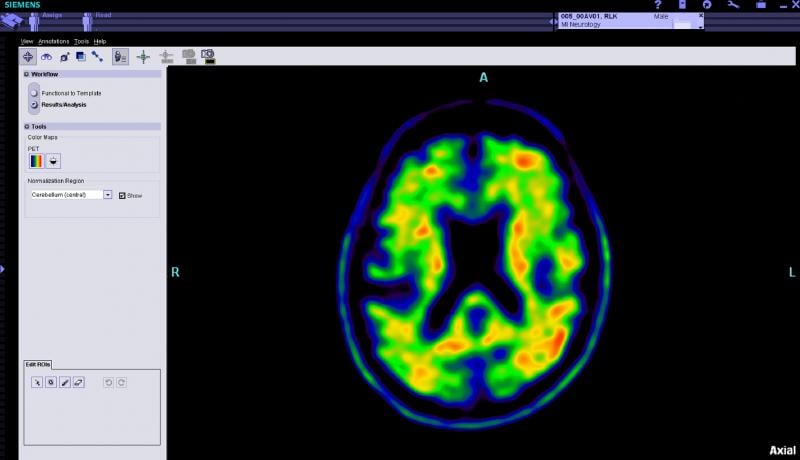

To recognize the advances in the field of nuclear and molecular imaging, as well as the professionals who carry out these procedures, the Society of Nuclear Medicine and Molecular Imaging (SNMMI) and the SNMMI Technologist Section (SNMMI-TS) celebrated Nuclear Medicine and Molecular Imaging Week, October 6-12, 2013. The theme of this year’s Nuclear Medicine and Molecular Imaging Week was “Molecular Imaging: The Future…Delivered.”